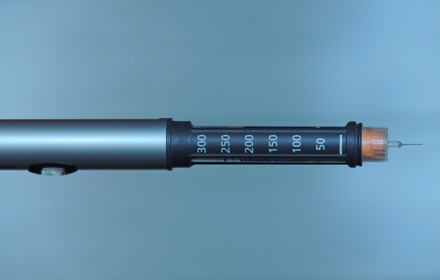

More training needed for delivering insulin

Tubeless insulin pump trialled at a London hospital

Online course on Understanding Insulin available now